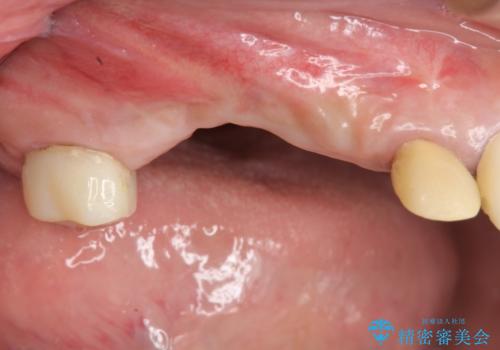

- 他院で1本インプラントを入れたまま治療に通うことができなくなり、途中からの治療を希望され来院されました。

既に埋入されているインプラントは位置が悪いのでそのまま骨内に留置することとし、新たに咬合機能を回復すべく3本のインプラントを埋入すると同時に吸収した骨幅を増やし、安定してインプラントで噛める環境整備を目指します。

- 120万円(インプラント×3 チタンカスタムアバットメント×3 メタルボンドクラウン×3 骨造成 歯肉移植)費用は治療当時の料金となります